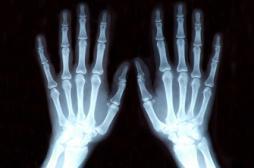

J ai Mal Bras et mains Bras et mains Tête et cou Torse et haut du dos Jambes et pied